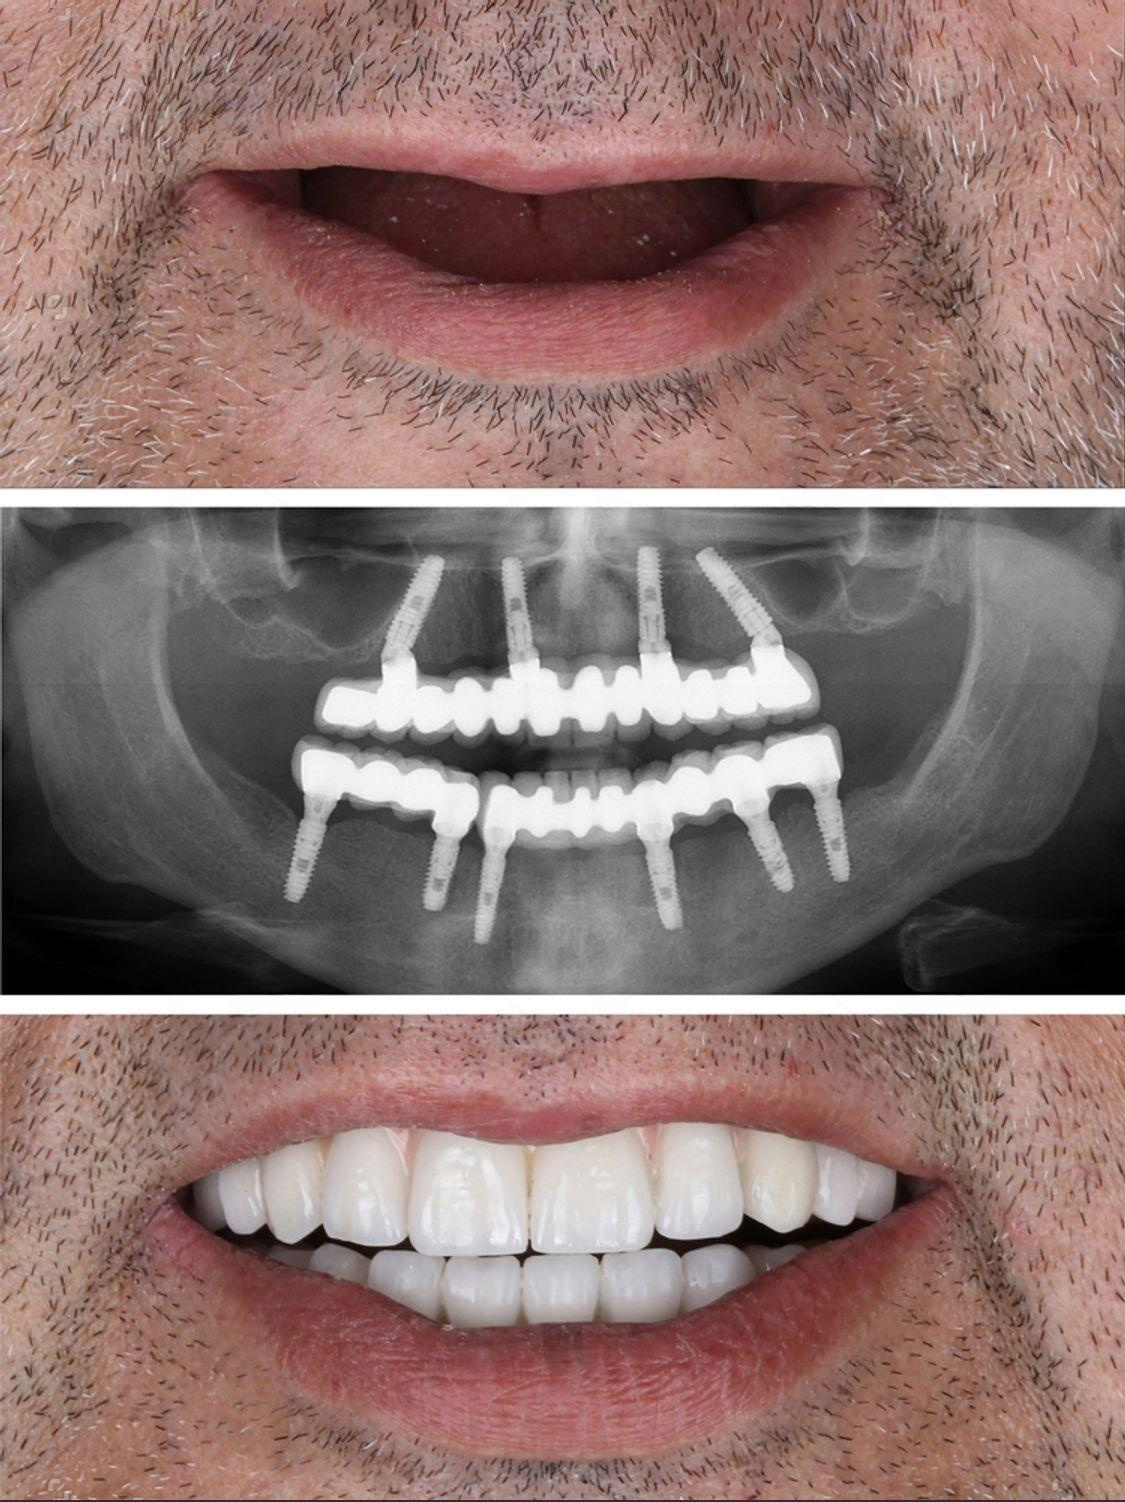

At Al Rayashi Dental Center, we believe that every smile tells a story — and we’re proud to be part of so many incredible journeys. Our Smile Transformations page showcases real patients who have trusted us to restore their confidence and enhance their dental health.

From subtle refinements to dramatic changes, these before-and-after cases highlight the power of expert care and advanced dental technology.